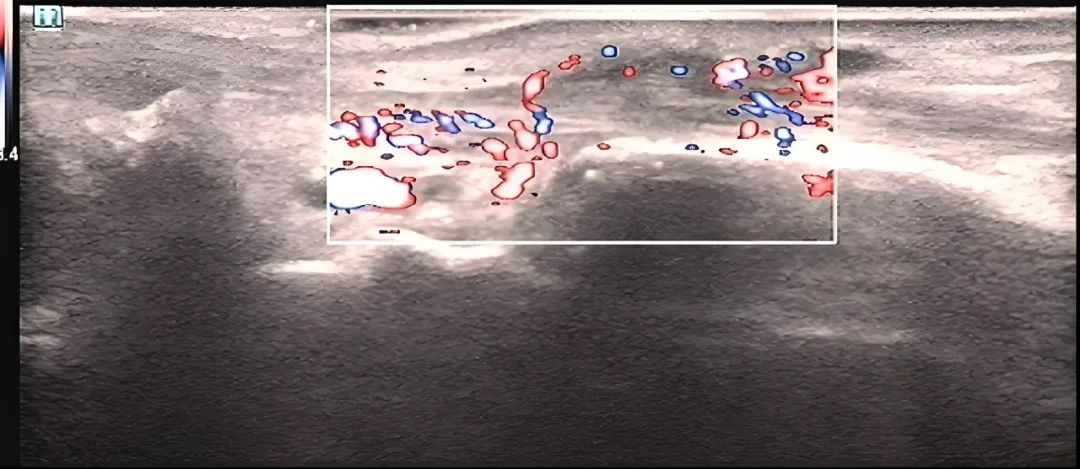

▲术前(腱鞘血流丰富)